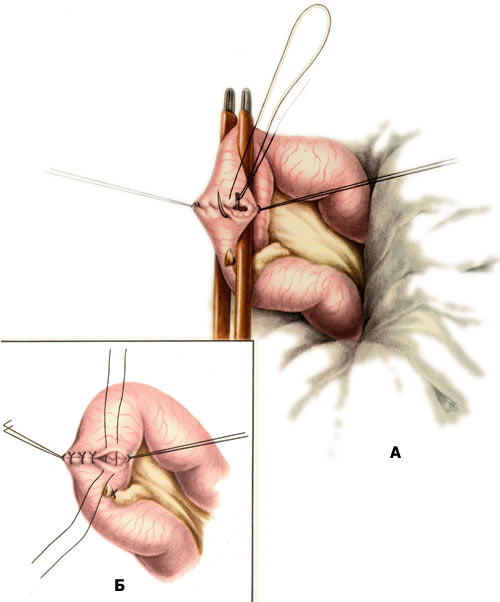

4. ЛЕЧЕНИЕ Бессимптомные дивертикулы удалять не следует. Дивертикул Меккеля подлежит удалению при дивертикулитах, язвах дивертикула, кишечной непроходимости, вызванной дивертикулом, свищах пупка, а также, по мнению ряда специалистов, при случайном обнаружении его во время операции. Производится резекция дивертикула с ушиванием стенки кишки (resectiodiverticuliMeckelii). Техника операции. После вскрытия брюшной полости извлекают подвздошную кишку вместе с дивертикулом. Если диаметр дивертикула небольшой, то техника удаления его ничем не отличается от обычной аппендэктомии. В тех случаях, когда дивертикул широкий и имеет брыжейку, последнюю перевязывают и пересекают, освобождая основание дивертикула. Затем на кишку накладывают мягкий кишечный жом и производят отсечение дивертикула у его основания (рис. 3). Рану кишки ушивают в поперечном направлении к ее оси двухрядным швом (рис. 4). Брюшную полость зашивают наглухо. Рис. 3. Резекция дивертикула Меккеля. Отсечение дивертикула. Рис. 4. Резекция дивертикула Меккеля. Ушивание дефекта в стенке кишки двухрядным швом: а — наложение скорняжного шва; б — наложение узловых серозно-мышечных швов. Прогноз благоприятный. 5. ЛАПАРОСКОПИЧЕСКИЕ МЕТОДЫ В ДИАГНОСТИКЕ И ЛЕЧЕНИИ ДИВЕРТИКУЛА МЕККЕЛЯ |